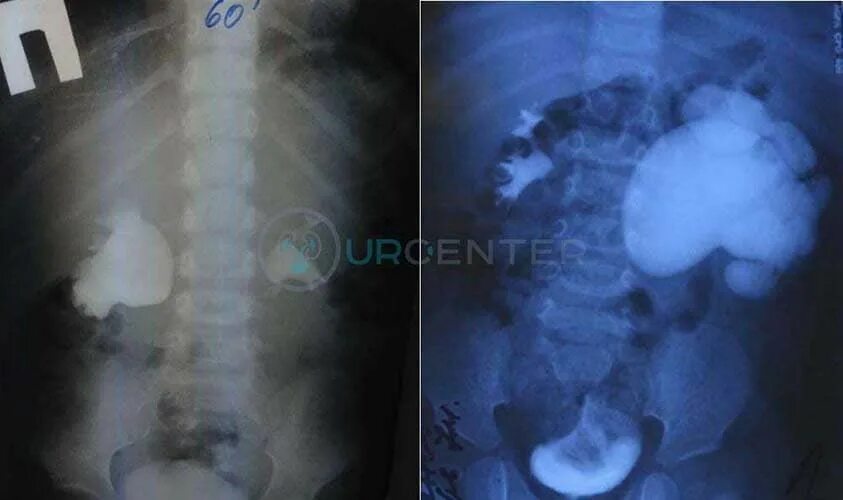

Гидронефроз почки после операции